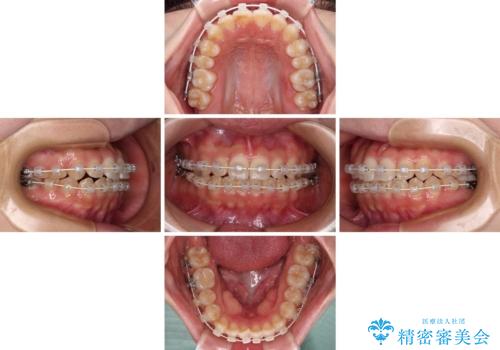

【モニター】短期間で終わりたい ワイヤー装置での非抜歯矯正

- 矯正装置

- 審美装置

- 1年1ヶ月

- 前歯のデコボコを気にして来院された患者様です。

マウスピース矯正のような自己管理の煩わしさがなく、早く治療を終えたいとのことで、ワイヤー装置による矯正治療を行うこととしました。

当初予定通り、1年で治療を終えることができました。

後戻り防止はマウスピースで行うため、急に自己管理が必要となるため、移動の最後をマウスピース矯正で行うことで、マウスピース非装着による後戻りリスクを回避する工夫をしています。